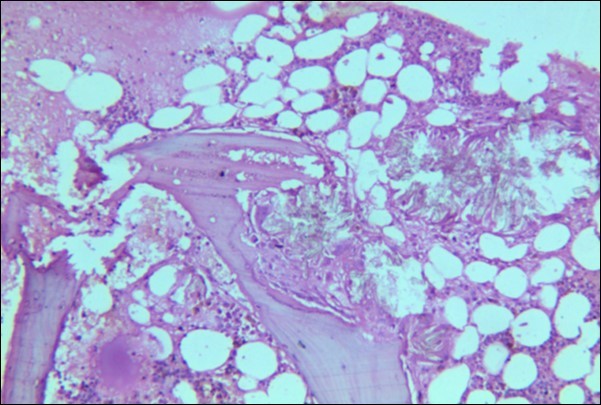

A 30 years old male, resident of Lahore was admitted for opinion regarding the necessity for regular hemodialysis after rejection of second renal transplant. Family history was suggestive of hereditary disease as two of his sisters had died of nephrocalcinosis leading to chronic renal failure at the age of 4 years. Consanguineous marriages in past many generations were also reported. Three cousins of the patient had recurrent stones with normal kidney functions. His past history revealed retention of urine at the age of 5 years due to stone in urethra. Patient presented again after 20 years in 2008 with retention of urine which was relieved by catheterization. Renal ultrasound and X ray KUB reported normal kidneys in both instances. Work up for stone formation was not undertaken at that time. The patient was put on hemodialysis and was planned for transplant which was undertaken in May 2009. After one month, follow up tests revealed Serum Creatinine to be 2.0 mg/dL. Renal Biopsy done in Sep 2009 revealed rejection of transplant. Hemodialysis was started and a second transplant was contemplated. Hemodialysis continued for 2 years till Dec 2011 when second transplant was carried out. A repeat renal biopsy was indicated for increasing serum creatinine. Again transplant rejection was evident on histology. Further investigations revealed Urinary oxalate excretion exceeding 40 mg/day (30 mg Oxalate/gram creatinine). His Blood investigations at the time bone marrow studies revealed bicytopenia with a Haemoglobin of 7.8g/dl, White blood cell count of 5.8 x 109/l; Platelet count of 120 x 109/l. Serum Creatinine was 3.6mg/dl. An attempt to correct the cytopenias by iron, vitamin B12 and folic acid supplements met with failure. No response to anemia could be elicited by adding erythropoietin to the treatment regimen. Renal and bone marrow biopsy were undertaken. Renal biopsy of the patient revealed crystals of calcium oxalate in the tubules (Figure 1). The same crystals were also visualized in bone marrow aspirate (Figure 2a and Figure 2b) and trephine biopsy (Figure 3).

Figure 2a & b.Photomicrograph of bone marrow aspirate from case I revealing oxalate crystals interspersed in the bone marrow fragments and a foreign body giant cell.

Figure 3.Photomicrograph of bone marrow core from case 1 showing radially arranged calcium oxalate crystals replacing haemopoietic tissue with invasion and destruction of bony trabeculae. Areas of necrosis and a cluster of hemosiderin laden macrophages is visible.